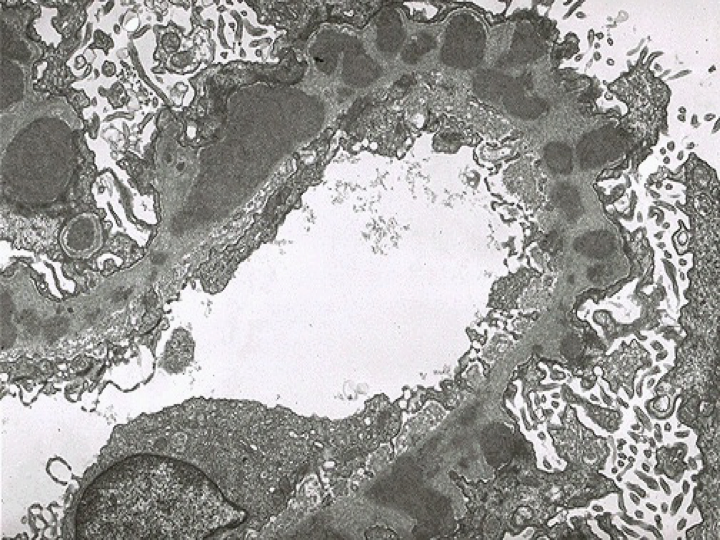

电镜下: 除证实肾小球内增生的细胞主要是系膜细胞和内皮细胞,渗出的细胞是中性粒细胞等外,可见基底膜外侧或上皮下有高密度、大团块电子致密物沉积。沉积物从基底膜向外侧形成驼峰状突起(hump)。